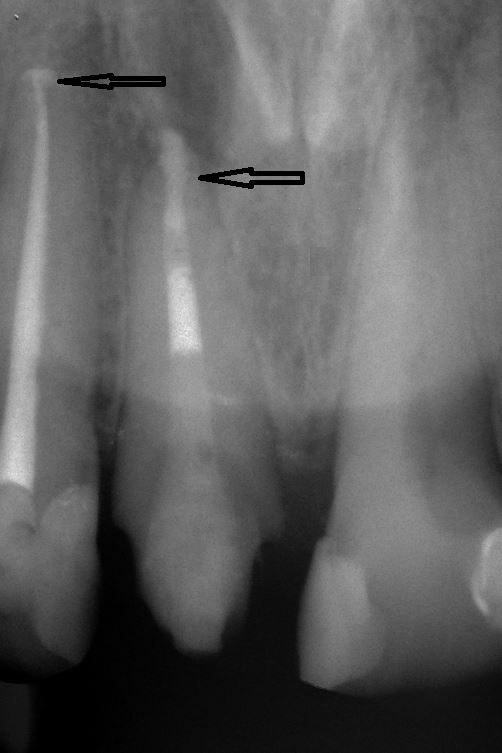

Fallbeispiel für einen Seitenrand

Fallbeispiel für einen komplexen Kanalverlauf

Normalerweise werden Wurzelkanalfüllungen bisher teilweise "nach Gefühl" durchgeführt, da der Zahnarzt den genauen Verlauf der Wurzelkanäle nicht immer eindeutig erkennen kann und kleinere Kanäle oft gar nicht aufzufinden sind.

Durch eine bis zu 24-fache Vergrößerung sind die Kanäle besser darstellbar und dadurch auch effizienter zu reinigen. Durch Reste von Pulpagewebe im Wurzelkanalsystem kann eine Entzündung entstehen, mit der Folge einer erneut notwendigen Wurzelkanalbehandlung oder dem Zahnverlust.

Der Einsatz des Mikroskops ist keine Garantie für den Erfolg einer Wurzelbehandlung , erhöht aber deutlich die Erfolgsquote und führt zu einem vorhersagbarerem Ergebnis.